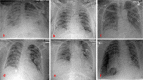

Results: Three thousand three hundred sixty-eight patients were admitted to our institution between March 1st, 2020 and June 8th, 2020 for suspected COVID 19 pneumonia, 902 patients were nasopharyngeal swab positive. Six cases of COVID-19 patients who developed spontaneous pneumothorax were identified (0.66%). Their baseline imaging showed diffuse bilateral ground-glass opacities and consolidations, mostly in the posterior and peripheral lung regions. 4/6 cases were associated with mechanical ventilation. All patients required placement of a chest tube. In all cases, mortality (66.6%) was not directly related to the pneumothorax.